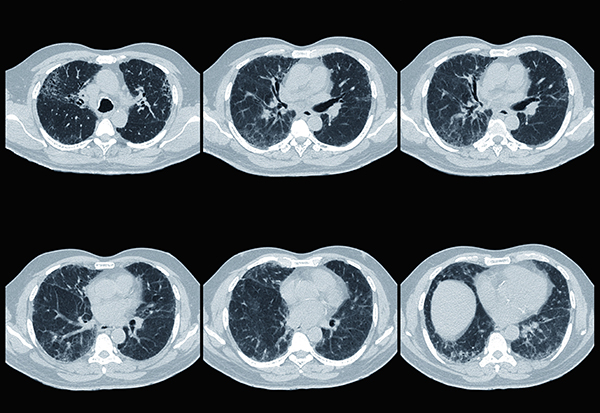

According to Dr. Martinez, ILD takes on a variety of forms and it is often difficult to understand if a patient has interstitial lung disease and what caused it. “To arrive at an accurate diagnosis requires taking a detailed history, performing a thorough physical exam, ordering the appropriate testing, including a high resolution chest CT, and reviewing imaging and biopsy results, if performed, with a team of specialists in ILD,” he says. “We work closely as part of a multidisciplinary team of pulmonologists, pathologists, and radiologists who meet bimonthly to review cases and make sure patients are getting the right diagnosis and the right treatment.”

“The Weill Cornell interstitial lung team encompasses many different subspecialties and allows us to apply our expertise at a very high level,” notes Robert J. Kaner, MD, a Weill Cornell pulmonologist and a leading expert in interstitial lung diseases. “In our testing, we’re looking for patterns of abnormality that would suggest that the gas exchanging part of the lung is being affected. Radiologists use terms like ground glass opacity, reticulation, architectural distortion, traction bronchiectasis, and honeycombing to describe some of the typical findings of ILD. The ones that indicate scarring are reticulation, traction bronchiectasis, and honeycombing. When we see those findings, we know that scarring is occurring in the lung and not just inflammation.”

“The best way to understand why people get pulmonary fibrosis is to study early disease in humans,” says Dr. Podolanczuk, whose work focuses on identifying individuals at the earliest stages of ILD and to conduct treatment studies before the disease becomes symptomatic. “We do that primarily by studying the progression of incidentally detected interstitial lung abnormalities, also called ILA, on CT scans done for other reasons. I collaborate with our expert thoracic radiologist to identify patients with early ILD who have undergone CT scans for lung cancer screening. We’ve also worked with large cohorts of patients who have been enrolled in cardiovascular disease studies and have repurposed their CT scans to look at the lungs.”

Dr. Podolanczuk investigates risk factors for early disease, both by visually assessing CT scans for interstitial changes, as well as using advanced computer-generated measures to detect very subtle changes. “We then try to identify new blood biomarkers that might be associated with these early interstitial changes,” she says. “We’re looking at high-density lipoproteins and the components of HDL, specifically apolipoprotein A1, as a protective factor and future therapeutic target. I’m also interested in environmental exposures and other acquired factors, and how they relate to the development and progression of pulmonary fibrosis.”